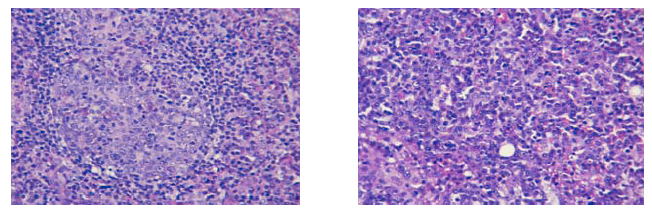

1. Many enlarged lymph nodes present in both hilar regions and mediastinum (largest measured 4cm in maximum dimension). Histology revealed proliferation of lymphoplasmacytic cells with architecture well preserved (Fig 4a & 4b).

2. Marked pleural adhesion was present in both sides, more severe in right side. Both lungs showed congestion and oedema. Consolidation of lung parenchyma with reddish appearance was present esp. in RML and BLL (Fig. 5a & 5b). There were also areas with septae thickening and polyclonal lymphocytic and plasma cells infiltrates, suggestive of lymphocytic interstitial pneumonitis (Fig 6a & 6b).